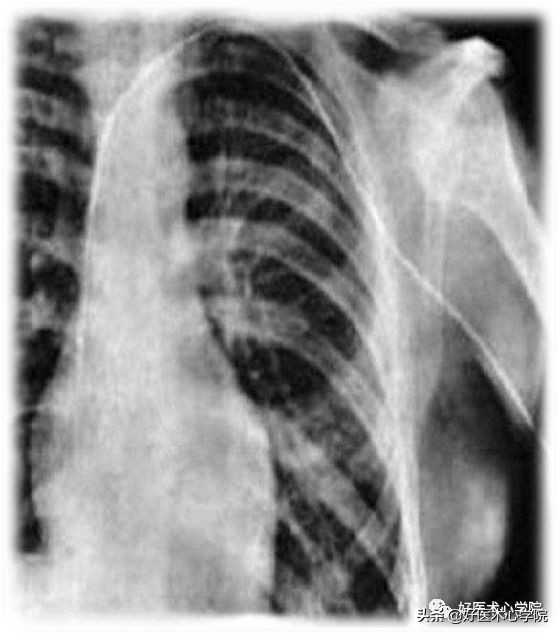

1929年,德国医生Forssmann首次将一根尿管从自己的肘静脉插入,经上腔静脉送入右心房,并拍摄下了医学史上第一张心导管胸片,开创了人类心导管技术发展的先河。